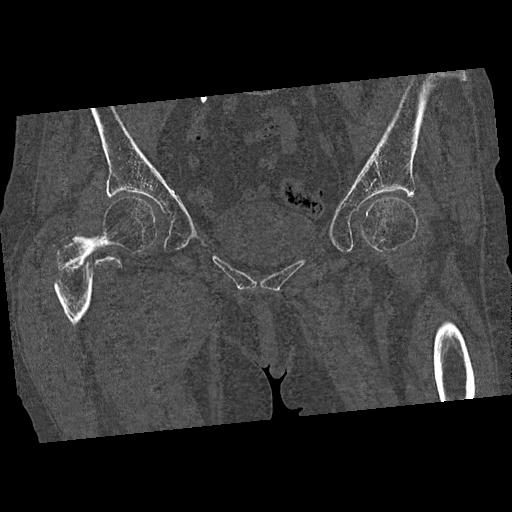

110286 2/17 股関節 2R 74歳女性 右人工骨頭

102903 股関節 2R 1/28 +股関節 2R 1/29 78歳女性 左人工骨頭

46666 1/28 両股正面+軸と 1/26 右手関節 2R 76歳女性 右転子部骨折

37 1/18 両股正面+軸 1/22 2R 86歳女性 右転子下

82084 1/14 1/20 股関節 2R 78歳男性 右人工骨頭

102811 1/13 股関節 2R 1/19 2R 80歳女性 右DHS

91569 3/25 両股正面とラウエン 70歳女性 人工骨頭+バンクーバー